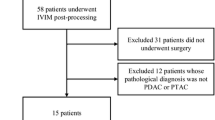

Sixteen subjects (14 white, 2 African American), ten men and six women with a mean age of 64 years, were accrued. All subjects had newly diagnosed, biopsy-proven pancreatic adenocarcinomas, and agreed to undergo pre-treatment MRI. Collected clinical data included tumor stage, grade, primary tumor location, single longest axis size measurement, and the presence of pancreatitis (as determined by histology in the surgically resected specimens).

Table 1 shows the characteristics of primary pancreatic tumors according to disease stage at diagnosis. Six subjects presented with synchronous liver metastases, three had locally advanced tumors, and seven presented with resectable disease. Nine subjects had pancreatic tumors in the head of the pancreas, two in the neck, two in the body, and three in the tail. The range of single longest axis tumor measurement was 1.4–4.8 cm, without statistical difference among disease stages. One of the subjects with locally advanced pancreatic cancer was successfully down staged by neoadjuvant chemoradiation therapy and underwent surgical resection. Seven among eight surgical specimens demonstrated tumor-associated chronic pancreatic inflammation. The presence or degree of pancreatic inflammation in the unresected subjects could not be determined histologically, as biopsy was directed toward the tumor. Fifteen subjects held their breath successfully during DWI (94%), and fourteen subjects coordinated repeated breath holding successfully during DCE-MRI (88%). Two subjects had liver metastases out of the Z axis longitudinal field of view (limited to 6 cm) of the DCE-MR images. Two liver metastases of each subject with DCE-MRI evaluable metastatic pancreatic cancer were randomly selected and analyzed (i.e., a total of eight liver metastases were analyzed).